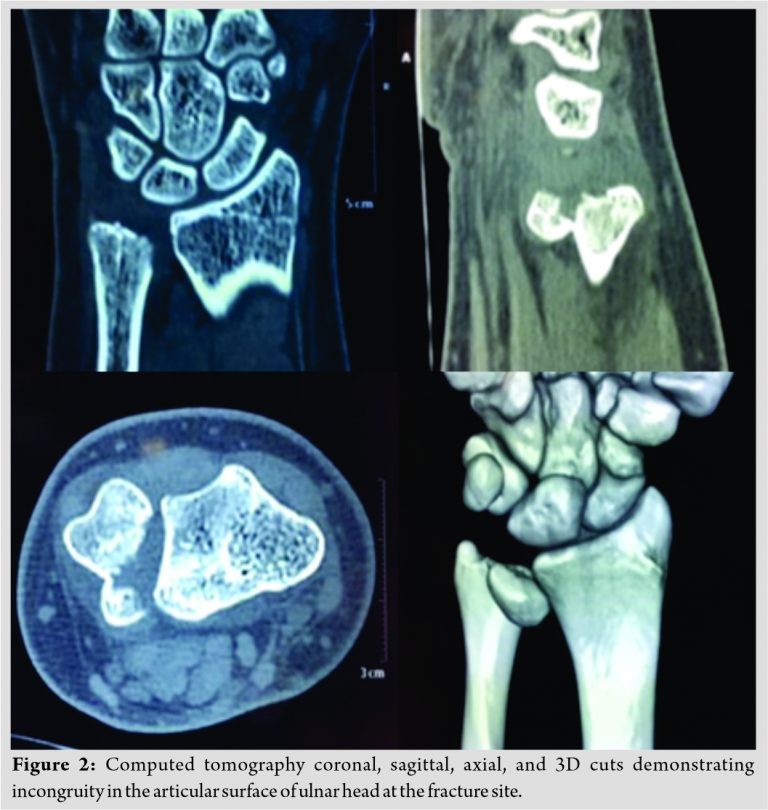

With respect to the clinical finding of a bony injury, an additional 3-D computerized tomography was done, on which there was an isolated intra-articular distal ulnar fracture with no disruption of distal radioulnar joint (Fig. 2). He was found to be having an isolated intra-articular distal ulna head fracture which was Q4 type according to AO Comprehensive classification [6].